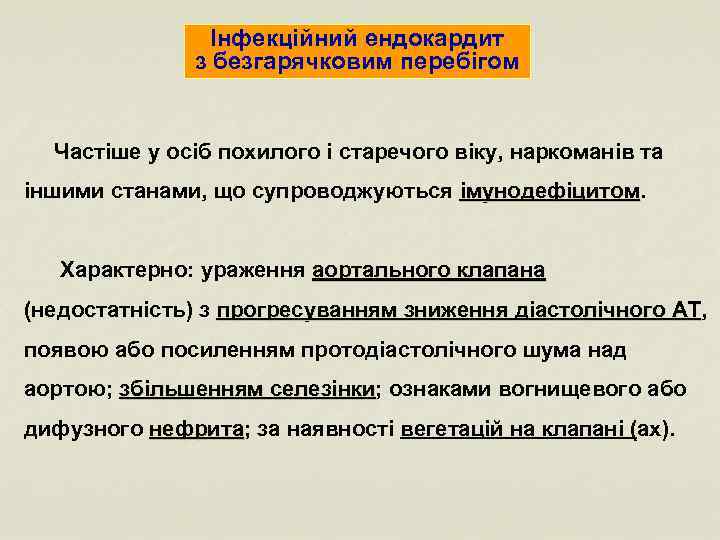

Інфекційний ендокардит з безгарячковим перебігом Частіше у осіб похилого і старечого віку, наркоманів та іншими станами, що супроводжуються імунодефіцитом Характерно: ураження аортального клапана (недостатність) з прогресуванням зниження діастолічного АТ, АТ появою або посиленням протодіастолічного шума над аортою; збільшенням селезінки; ознаками вогнищевого або селезінки дифузного нефрита; за наявності вегетацій на клапані (ах). нефрита